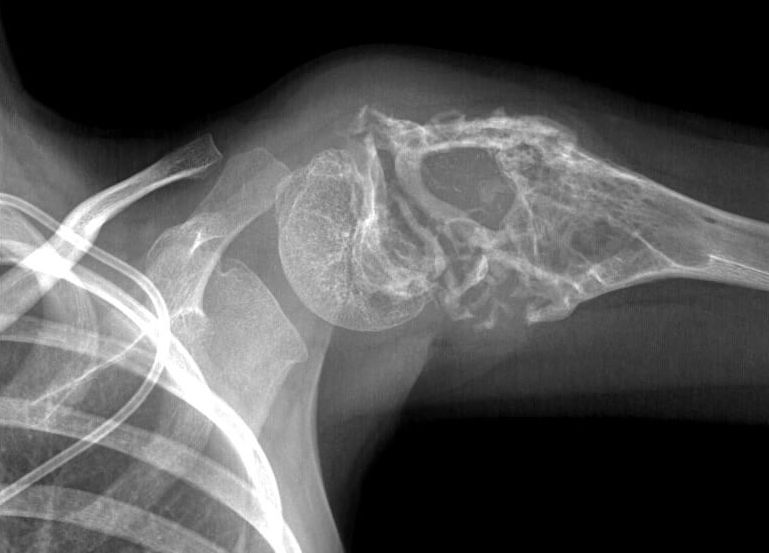

Рак Кости Фото

Рак Кости Фото 77 фото